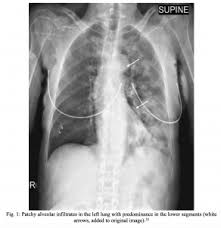

Also known as Mendelsons syndrome pulmonary acid aspiration syndrome is a dangerous condition in which acid and other stomach contents may enter the airway and ultimately the lungs. Acid aspiration causes alveolar and interstitial inflammation with edema and leukocyte infiltration. If the aspirated material is infected it is likely to cause pneumonia and lung abscess but if sterile and highly acid the consequences are liable to be even more dire.

72 Aspiration Pneumonia Mendelson Syndrome Radiology Key

Aspirationis when something you swallow goes down the wrong way and enters your airway or lungs. There is profuse frothy bloody sputum cyanosis and signs of air hunger tachycardia and fever. Pulmonary acid aspiration syndrome synonyms pulmonary acid aspiration syndrome pronunciation pulmonary acid aspiration syndrome translation English dictionary definition of pulmonary acid aspiration syndrome. Of relating to or affecting the lungs. Of or relating to or affecting the lungs 2. Pulmonary aspiration of gastric contents is a frequent event in unconscious or semiconscious patients. Acid aspiration causes alveolar and interstitial inflammation with edema and leukocyte infiltration. Antonyms for pulmonary acid aspiration syndrome. Aspiration syndromes include all conditions in which foreign substances are inhaled into the lungs.